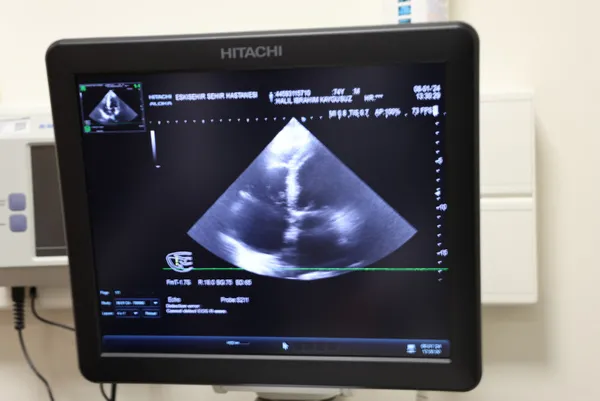

Birçok hastanede açık kalp ameliyatına alınan hastaların 2 ila 4 saat kadar operasyon geçirdiğini, fakat Eskişehir Şehir Hastanesi'nde bu sol atriyal apendiks kapama işlemini kesi olmadan 30 dakikalık müdahale ile tedavi ettiklerini belirten Kardiyoloji Uzmanı Doçent Dr. Özge Turgay Yıldırım, "Biz bu işlemde ritim bozukluğu olan yüksek riskli bazı hastalarda yapılan bir işlemi gerçekleştirdik. Bu işlem bölgemizde çok sık yapılan bir işlem değildir. Biz bu hastamıza 'Sol Atriyal Apendiks Kapatma' işlemi yaptık, tekrarlayan inmeleri olan ve mağduriyet yaşayan bir hastamızdı. Kan sulandırıcı tedavisini almasına rağmen inme tekrarlıyordu, bu yüzden bu işlemi yapmaya karar verdik. Hastamızda ritim bozukluğu var. Bu ritim bozukluğu kalbin içindeki kulakçıkta 'apendiks' dediğimiz bir kesecik içinde pıhtı birikmesine neden olan bir hastalık ve kalp kaynaklı inmeye neden oluyor. Biz bu kese ağzını bir şemsiye yardımıyla kapatabilirsek, bu bölgeden pıhtı atmasını ve felç geçirmesini engellemiş oluyoruz. Normalde bu işlem açık kalp ameliyatı ile de yapılabiliyor ama bizim farklı olarak yaptığımız kasıktan anjiyo gibi plastik bir iğneyle girerek ve buradan ilerleyerek, sol kulakçığın içine girip, oradaki keseciği bir şemsiye benzeri malzemeyle kapattık. Yani herhangi bir kesi olmadan kasıktan iğne yardımıyla bu işlemi yapmış olduk ve hastamızın tekrar kalp kaynaklı inme riskini çok ciddi derecede azaltmış olduk. Bu ameliyatı açık kalp ameliyatı şeklinde yaparsak önce kemiği açmamız ve kalbin içerisine girmemiz gerekiyor. Hatta kalbi kesmemiz daha sonraysa orayı kapatmamız ve bağlamamız gerekiyor ama biz bu işlemi iğneyle kasığı uyuşturarak yapıyoruz. Bu işlem yaklaşık 15 ila 30 dakika arasında sürüyor. Hastamız ise günübirlik bir yatış sonrası taburcu olabiliyor. Eğer açık kalp ameliyatı şeklinde yapılırsa hastamızın en az bir hafta yatması gerekir, onun haricinde işlem 2 - 4 saat arası sürebilir, ameliyatın içerik ve tipine göre değişir. Gerçekten pıhtı kalp içinde bu kesecikten kaynaklıysa biz zaten bu kesenin ağzını kapatıyoruz, bu durumda bu pıhtının buradan çıkıp gitmesi teorik olarak çok zor. Çok nadir olarak tekrarlayabilir tabi ama bu hastalar normalde ömür boyu kan sulandırıcı tedaviye mahkum hastalardır, biz burayı kapattığımızda kan sulandırıcıları dahi kesebiliyoruz. En önemli artısı bu ve hastamız tekrar inme geçirmiyor. Hastamız bu işlemden sonra şikayetlerinin gerilediğini, tekrar baş dönmesi ve dengesizlik şikayetlerinin olmadığını söyledi. Klinik olarak da fayda gördük" dedi.